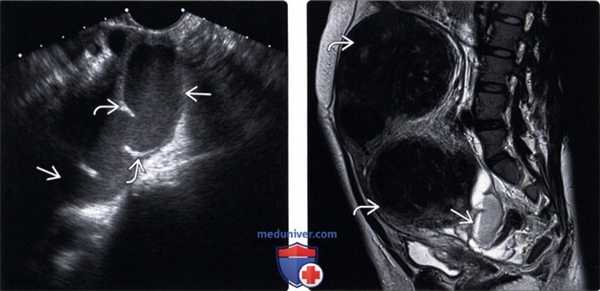

(Слева) Трансвагинальная уль трасонография в продольной плоскости; визуализируется расширенная болезненная фаллопиева труба, содержащая низкоуровневые эхосигналы и неполную перегородку. Такие признаки характерны для пиосальпинкса.

(Справа) MPT, Т2, TSE, сагиттальный срез у этой же пациентки; определяется уровень детрита в пиосальпинксе. Бесчисленные крупные фиброиды было трудно оценить при ультрасонографии.